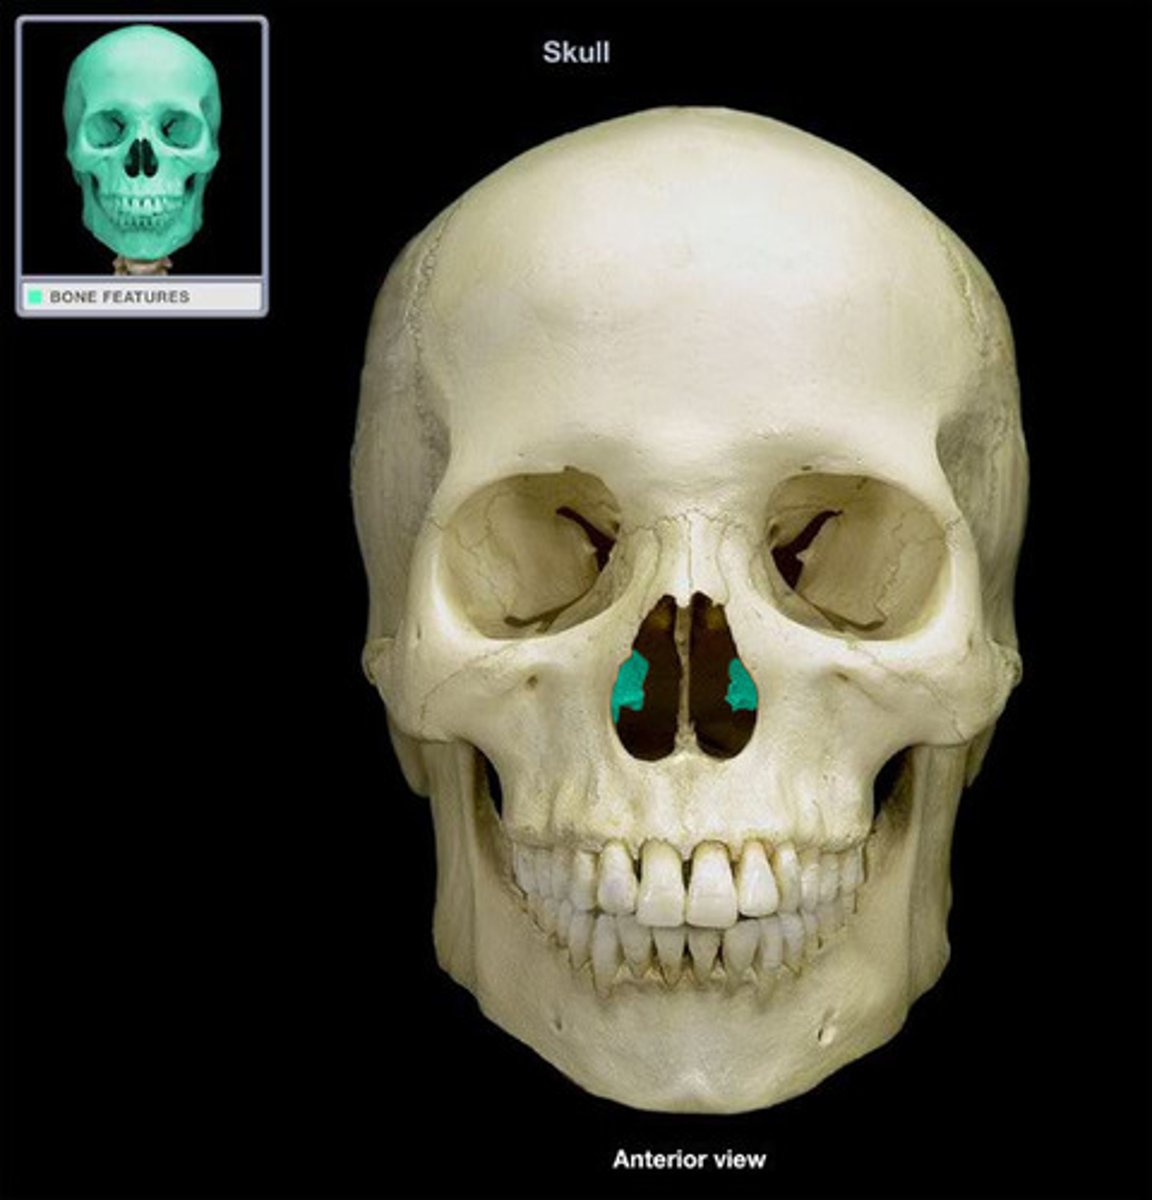

Vomer Bone

Flat, thin bone that forms part of the nasal septum

Nasal Conchae

Two bones that help to complete the nasal cavity by forming the side and lower wall